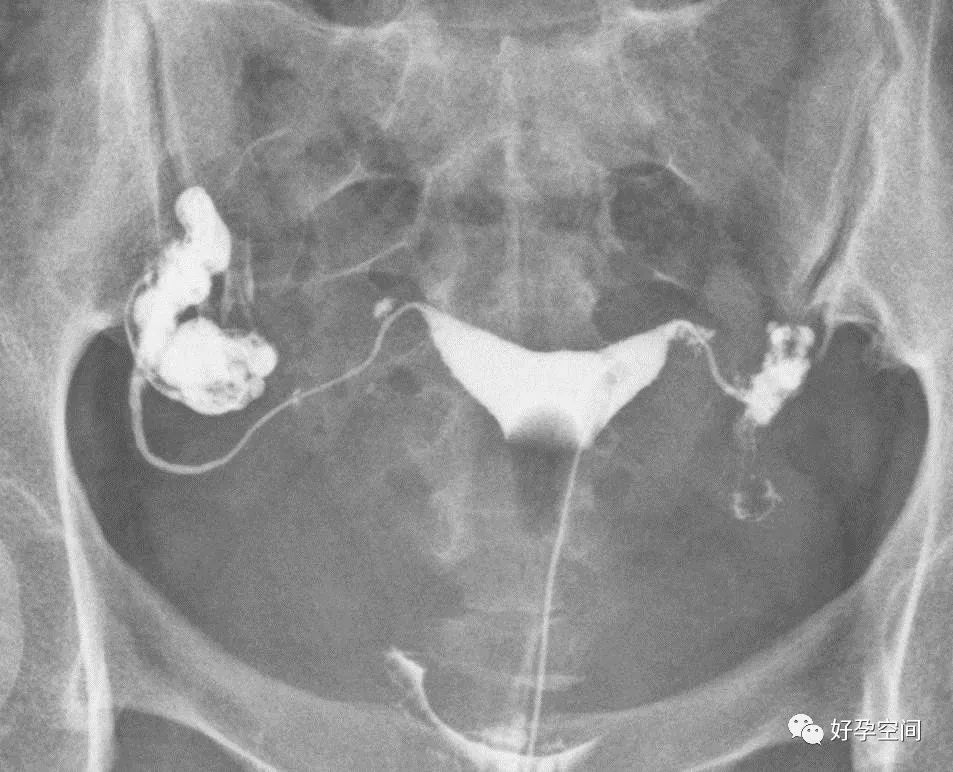

弥散相,延迟5分钟摄片,双侧输卵管内可见较多造影剂

弥散相,延迟10分钟摄片,双侧输卵管内可见少量造影剂

弥散相,延迟20分钟摄片,双侧输卵管内基本没有造影剂残留